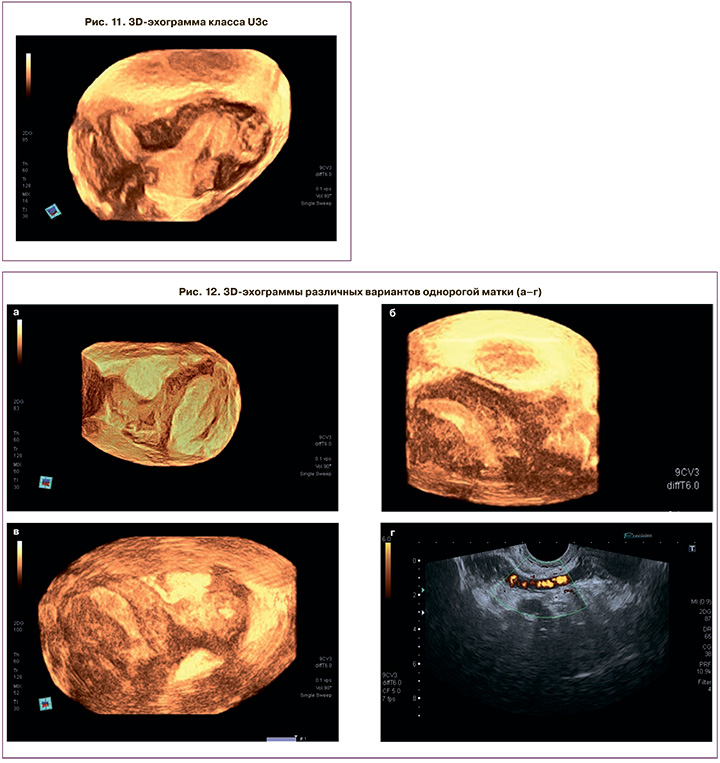

Ультразвуковые паттерны класса U3с позволяют наглядно оценить возможность гистероскопической коррекции порока для формирования адекватной полости, но только под интраоперационной ультразвуковой навигацией (рис. 11).

Самый большой процент диагностических и тактических ошибок касается класса U4, объединяющего различные однорогие матки. 3D-критериями в ФС стали: уменьшенный поперечный размер матки (от 20 до 24 мм), полигональная форма НКМ, «бананообразная»/Г-образная форма полости, асимметричное расположение яичников. Важной является панорамная оценка зоны параметрия для идентификации дополнительного рога в виде структуры, расположенной справа или слева от основного рога, контактирующего с ним и имеющего различную форму – от полигональной до линейной, объемом, не превышающим 1/3 объема основного рога. Добавочный рог, помимо полигональной формы, может иметь различную структуру: от однородной средней эхогенности без активного кровоснабжения до гиперваскулярной гетерогенной структуры. Важной является идентификация функциональной способности рога за счет обнаружения полости с эндометрием, что ни в коем случае не должно быть пропущено, поскольку данная аномалия колоссально повышает риск эктопической беременности с возможными грозными осложнениями и снижает возможность ее диагностики, а также повышает риск заболеваний эндометрия или формирования гематосальпинкса (рис. 12). Только проведение 3D-ГСГ позволит определить наличие сообщения между основным и добавочным рогом в виде затекания контраста из основной полости в рудиментарную. Всем пациенткам данного класса в незамедлительном порядке мы рекомендовали проведение лапароскопии, удаление рога с маточной трубой.